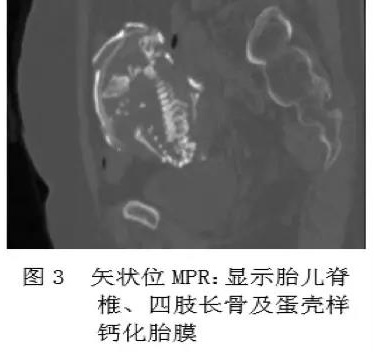

石胎的主要诊断手段是影像学检查,包括 B 超,X 线和 CT 等。超声下可见高回声光团和胎儿结构回声,X 线可以看到胎头、脊柱、肋骨及四肢等结构,CT 表现可见钙化的胎膜和胎儿(见下图)。

石胎 CT 图像

(图片来源:邓小强. 腹腔石胎 1 例. 中国医学影像技术 2010, 26( 11))

鉴别诊断有难度时,可以考虑进行多层螺旋 CT(MSCT)扫描,更能直观、多方位、多角度地显示脊柱、肋骨、四肢及胎膜钙化情况,为临床提供准确的影像信息(见下图)。

图片来源:吴德红等. MSCT 对腹腔石胎的诊断价值. CT 理论与应用研究, 2015, 24(1): 129-134.